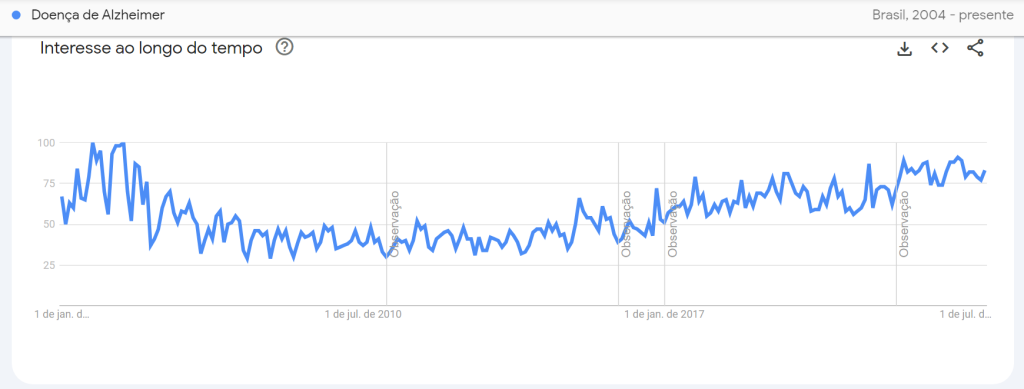

De acordo com dados levantados na plataforma desde 2004, os anos de 2019 e 2022 compõem os de maior número de buscas no mundo sobre a doença. O valor de 100 presente no gráfico de pesquisa representa maior pico de popularidade de um termo. Um valor de 50 significa metade da popularidade e a pontuação pontuação de 0 significa que não havia dados suficientes sobre o termo.

Já no Brasil, os anos de pico das pesquisas sobre Alzheimer correspondem a 2004 e 2005, seguidos por 2022, que registrou pontuação de 89 em março.